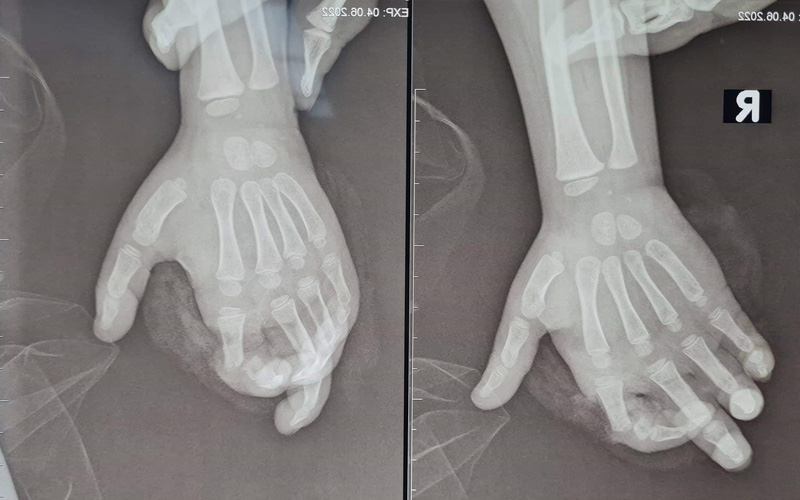

TS.BS Nguyễn Quang Vịnh, Khoa Phẫu thuật Chi trên và Vi phẫu thuật, Bệnh viện Trung ương Quân đội 108 cho biết: Kết quả thăm khám xác định bệnh nhi vào viện giờ thứ 4 do bị máy nghiền hoa quả nghiền vào bàn tay phải. Sau tai nạn, bệnh nhi bị đứt gần rời ngón 2 tay phải, phần ngón đứt gần rời lủng lẳng, trắng bệch do không được cấp máu.

Các bác sĩ phải kết lại xương, khâu nối gân duỗi, nối thần kinh và đặc biệt là phải nối lại mạch máu (gồm các động mạch và tĩnh mạch) để cung cấp lại máu cho ngón tay. Do kích thước mạch máu ở trẻ em rất nhỏ, tổn thương lại do máy nghiền, bầm giập nhiều nên việc trồng lại ngón tay cho bệnh nhi là rất khó khăn.

Sau phẫu thuật, tình trạng bệnh nhi vết thương khô, ngón tay 2 hồng hào.